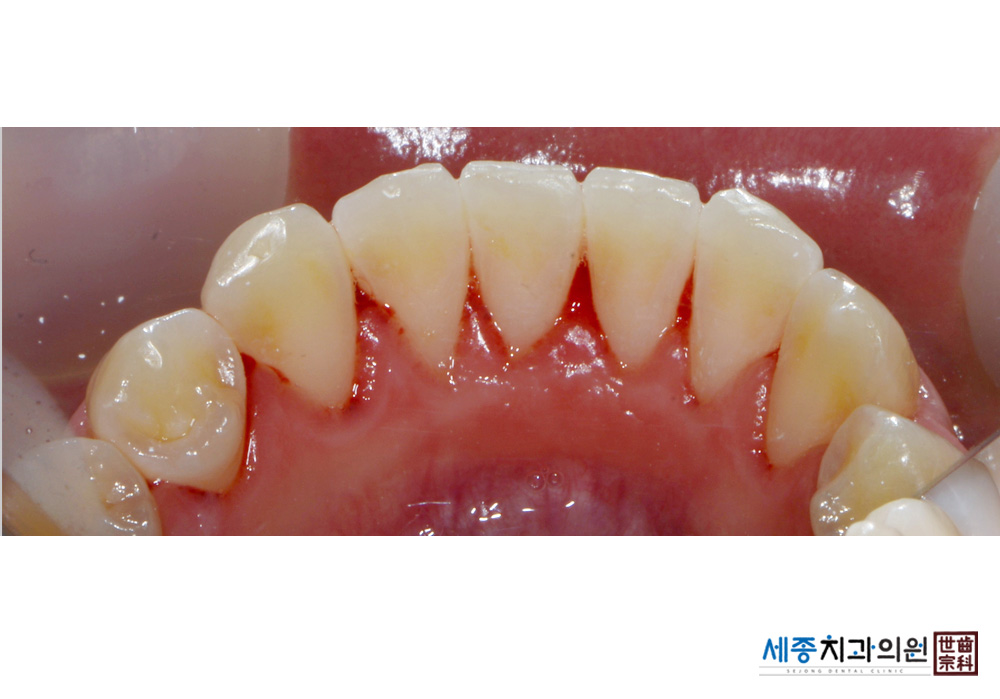

[스케일링] 치주질환 예방 스케일링 치료

치료후 : 2016-10-28

가글마취&저주파 스켈러를 사용한 스케일링